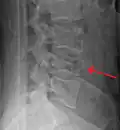

A burst fracture of L4 as seen on CT